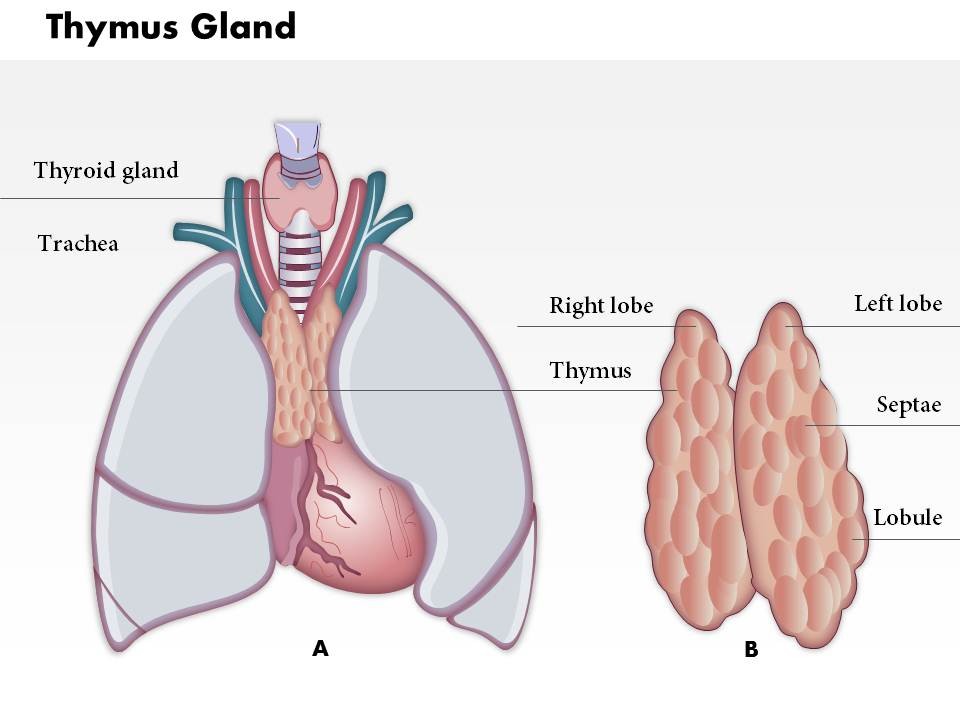

Фотографии вилочковой железы тимуса: структура и функции